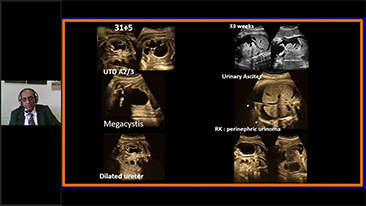

Con la tecnologĂa de la avanzada plataforma ZST+, las soluciones inteligentes completas de la serie Nuewa estĂĄn dise?adas especialmente para mejorar la salud de las mujeres durante el perĂodo previo al embarazo, el embarazo y la recuperaciĂłn en el posparto, con el fin de brindar diagnĂłsticos integrales y eficientes para enfrentar desafĂos clĂnicos cada vez mĂĄs exigentes.

Productos para la salud de la mujer